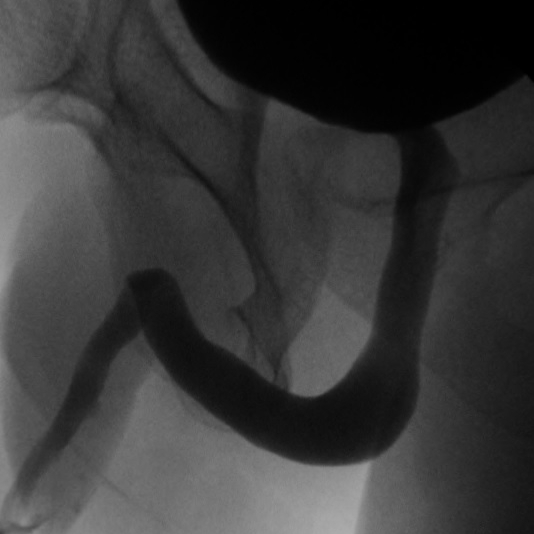

Retrograde Urethrogram / Voiding Cystourethrogram. A retrograde urethrogram (RUG) and Voiding cystourethrogram (VCUG) are two X-ray studies that provide valuable information to determine the length and location of your urethral stricture. A RUG is performed by injecting a contrast material backward into the urethra. The RUG provides great information on the anterior urethra, however provides very little information on the posterior urethra. A VCUG is performed first by passing a small catheter past your scar and into the bladder. The bladder is then filled with more contrast material. The catheter is then removed and X-rays are taken while you begin to start urinating. The VCUG provides valuable information on the posterior urethra.